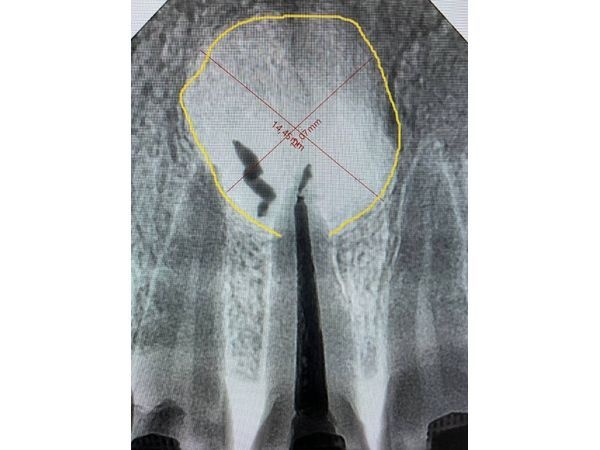

КТ на верхушке корня показала округлое образование диаметром 12,07 мм и немного пломбировочного материала за апексом (местом, где канал соприкасается с твёрдой верхушкой). Сам канал запломбирован хорошо (без дефектов, нерв удалён полностью).